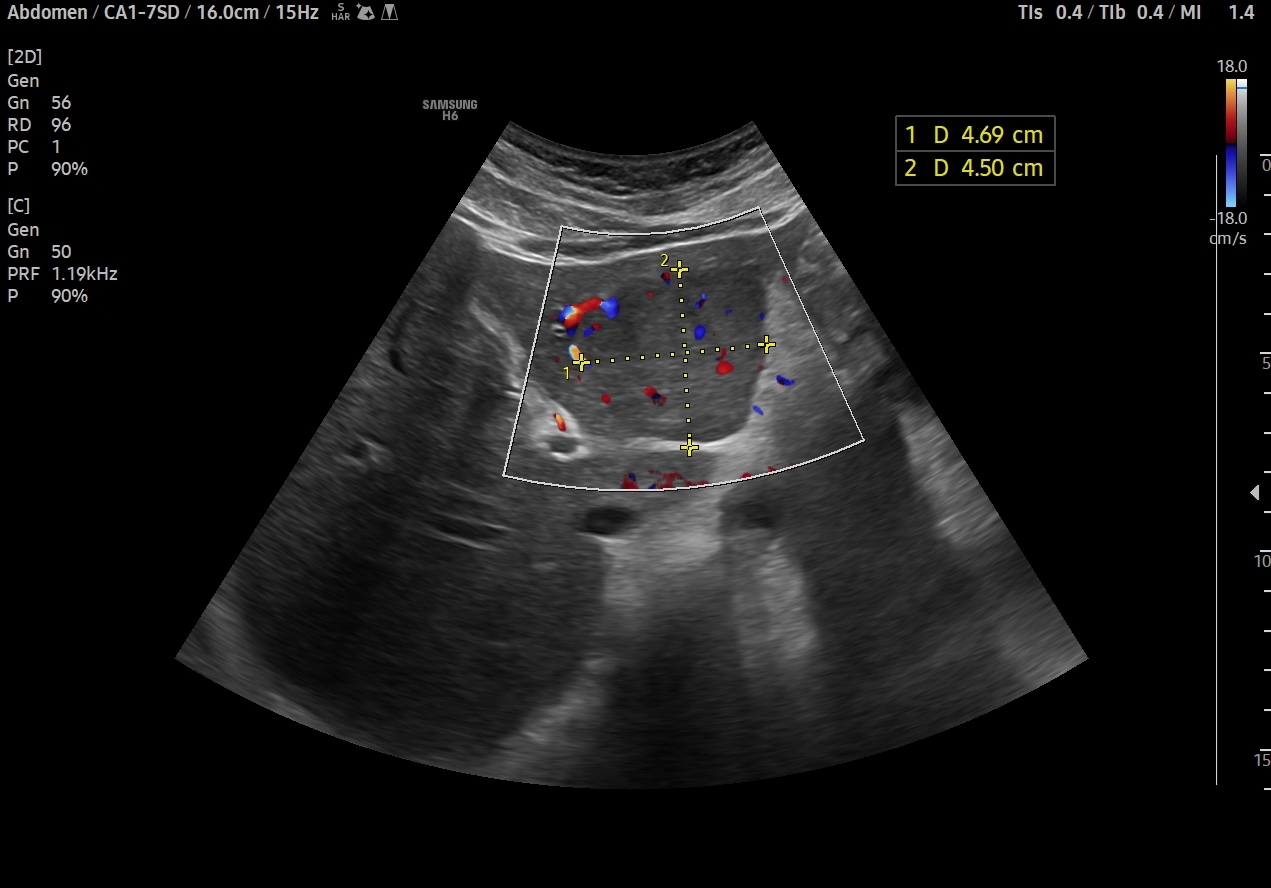

En el lóbulo hepático izquierdo visualizamos lesión focal iso-hipoecogénica respecto al parénquima hepático circundante que mide 4,6 x 4,5 x 3,9 cm y que presenta un aumento de la señal Doppler. Vemos la imagen tanto en cortes transversales como en cortes longitudinales, también con el modo Doppler activo. Resto de parénquima hepático y vía biliar de aspecto normal, sin otras alteraciones.